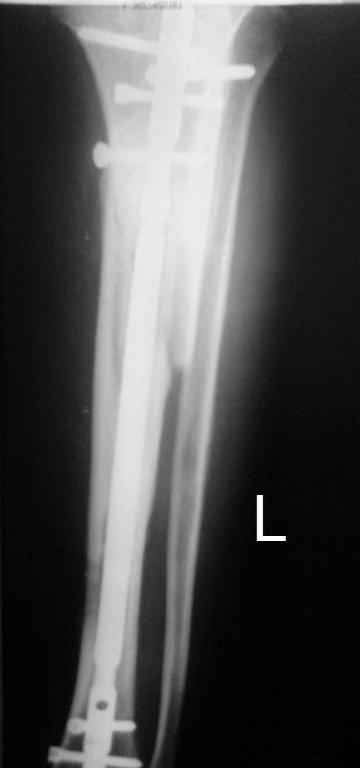

Выкладываю картинки похожей пациентки. Извините, что без окончательных снимков (сейчас их нет под рукой). Правда мы имели проблемы у данной больной после снятия аппарата, когда промежуточный фрагмент большеберцовой кости сместился на 1,5 см дистально и отошел от проксимальной части кости. До сих пор у пациентки на снимках определяется лишь тонкая полоска кости по задней поверхности за штифтом (образовалось что-то вроде маленького регенерата)в области стыковки промежуточного и проксимального фрагментов. Больная пока решила подождать. Не хочет оперироваться, так как ходит не хромая, работает.

Кратко: мужчина за 60 лет получил травму 28 лет назад (переехало автобусом). Оперировался десятки раз, в итоге с очередным патологическим переломом, хронической язвой и гипсовой лонгетой попал ко мне... Объективно - остеомиелит, инфицированный ложный сустав (или как его назвать), флегмона по наружной поверхности

голени, укорочение около 5 см.

На операции резекция 8 см, внешний остеосинтез,одновременное сближение примерно на 4 см, а затем постепенное сближение до полного контакта в течение 3 недель. Рана с патологически измененными краями, имевшая на операции размеры примерно 4-5 на 10-12 см закрылась самостоятельно в течение примерно 2-х мес. Ну не самостоятельно, конечно, а с нашей помощью, но без пластики.

Сейчас в аппарате вытянул около 6 см в верхней трети.